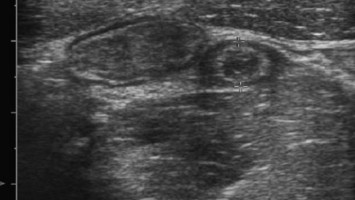

Kind mit "Bauchweh": Liegt die Ursache eine Etage tiefer?

In der pädiatrischen Notaufnahme sind „Bauchschmerzen“ mit der häufigste Vorstellungsgrund. Dabei liegt die Ursache nicht selten eine Etage tiefer.